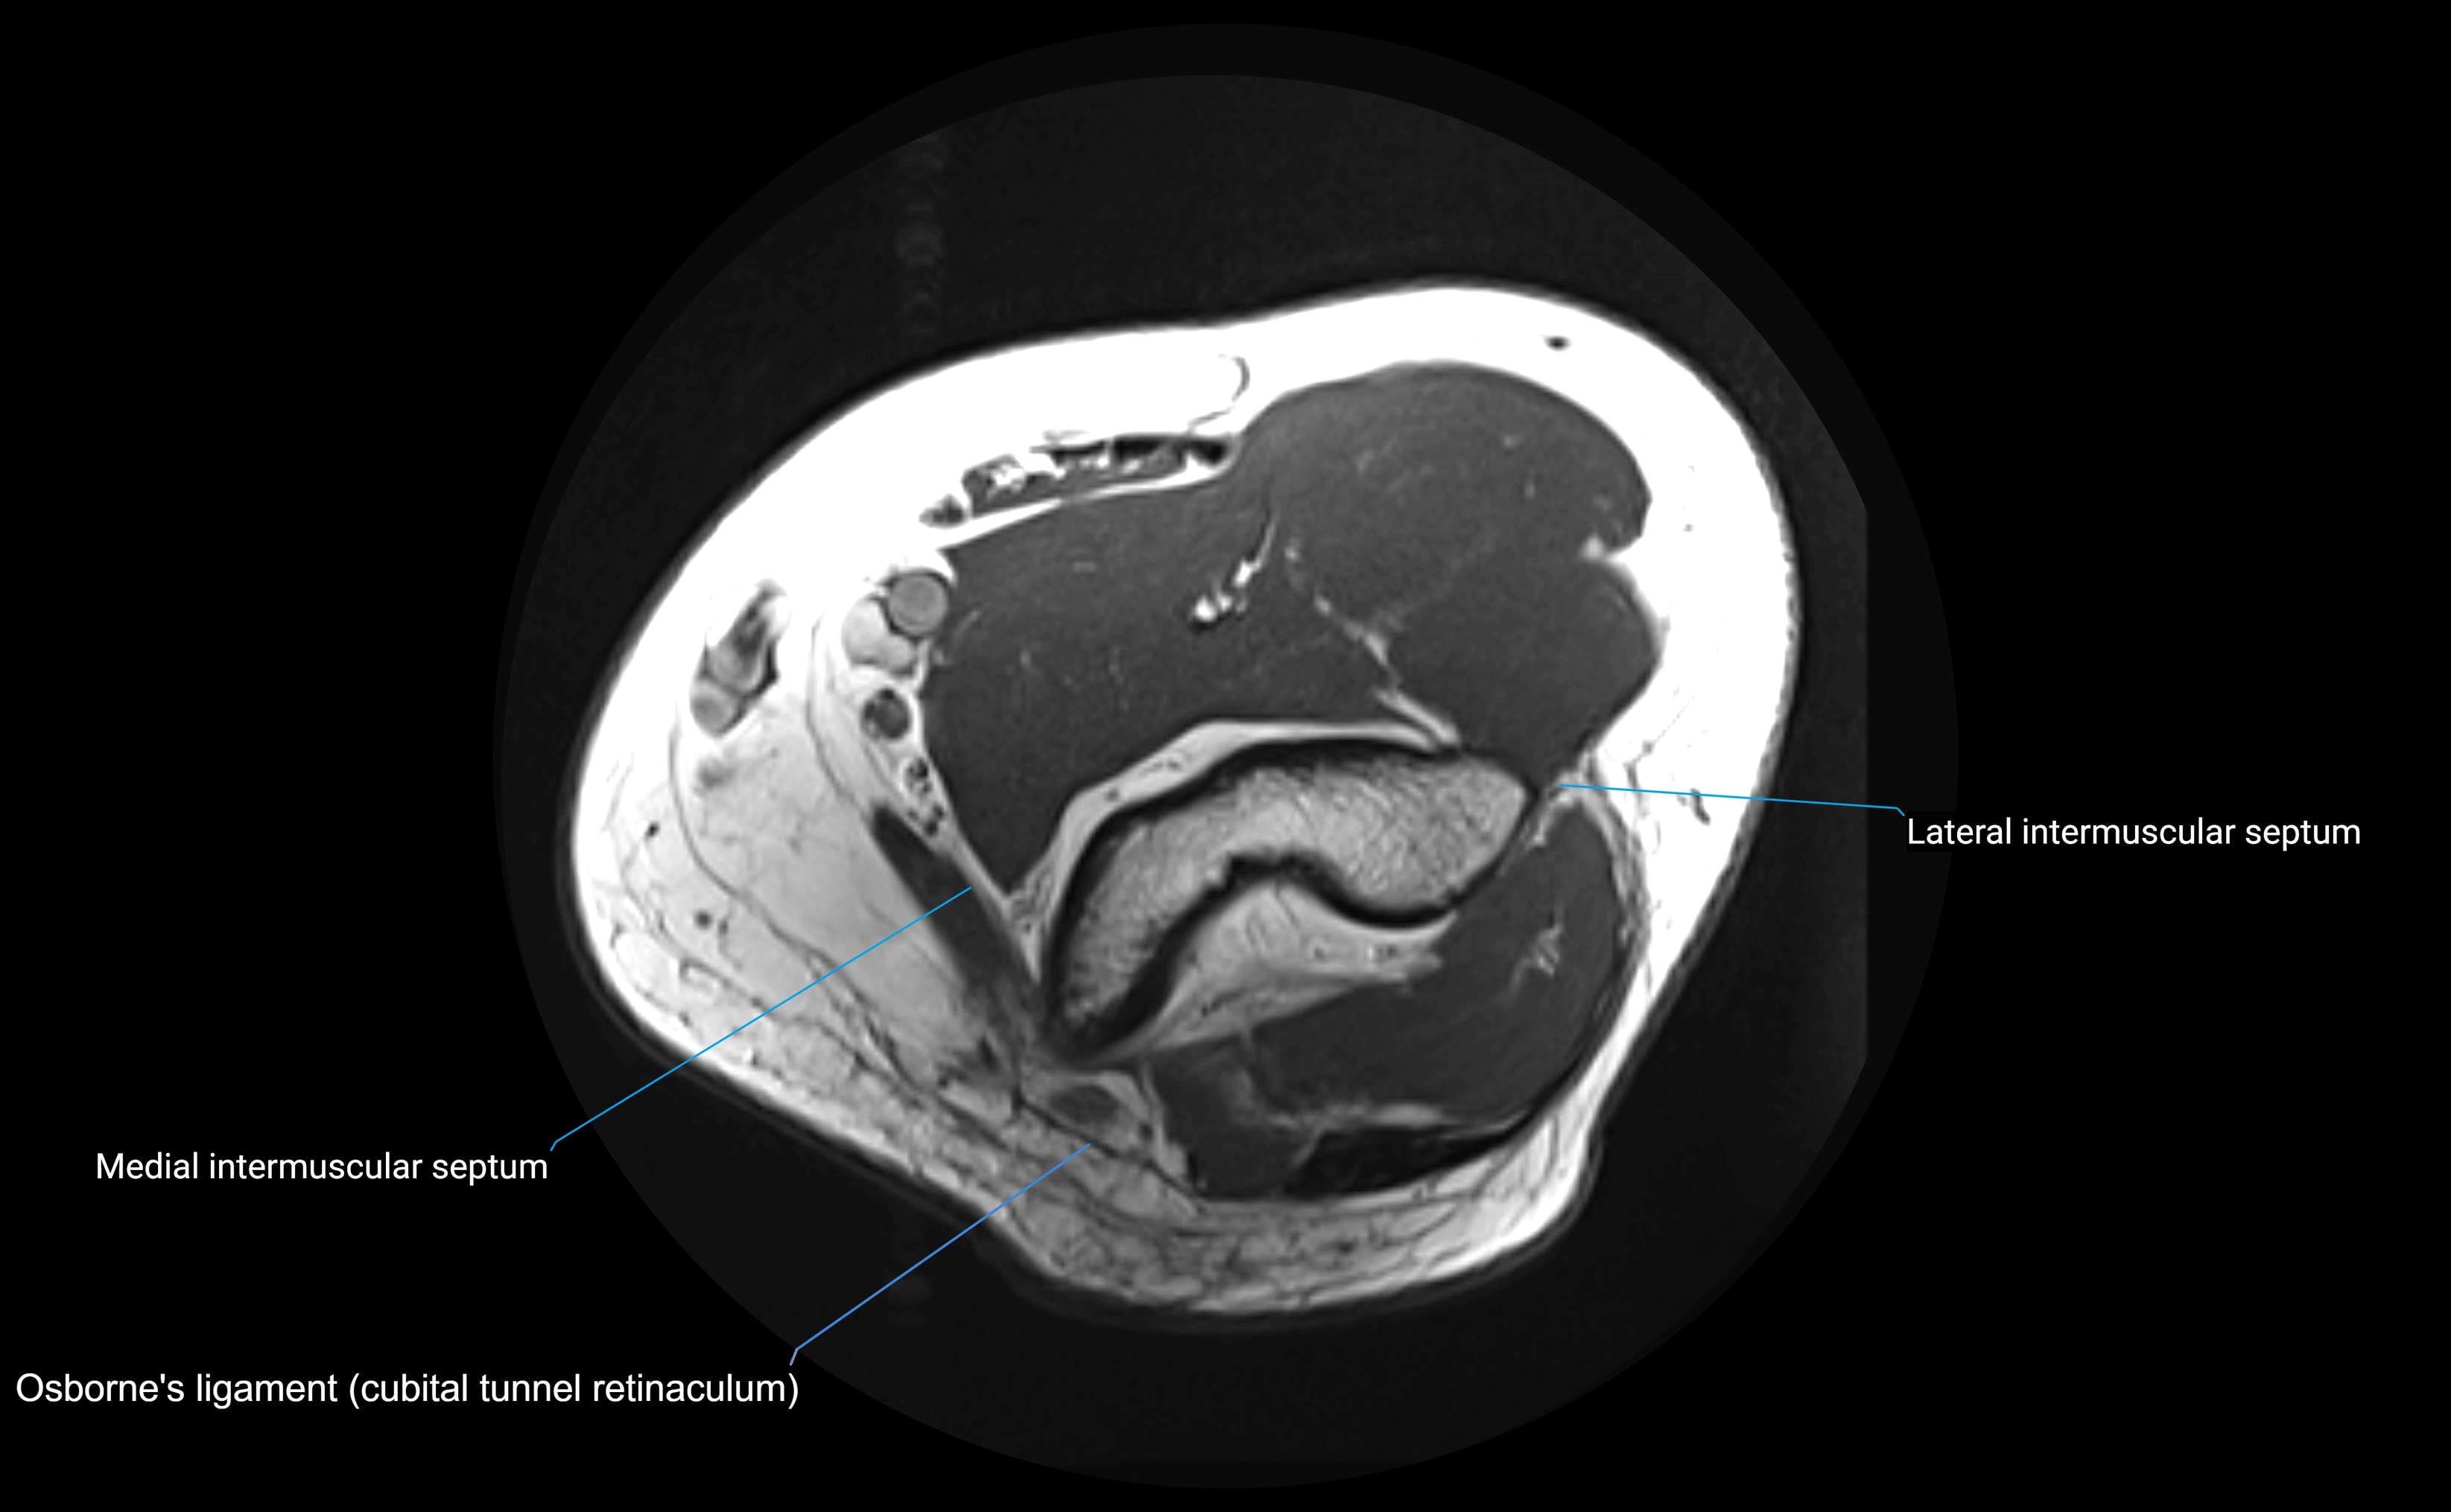

MRI images

image